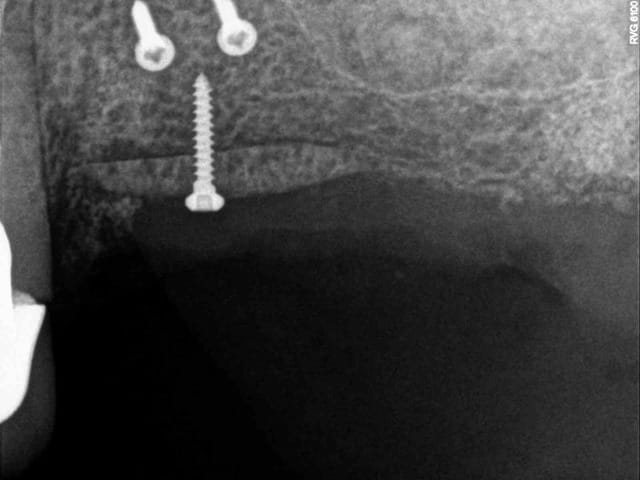

les vis STOMA de 1mm de diamètre j'adore !

ici, avec le sinus lift réalisé avec le DASK (merci Michael B.) et avec la greffe d'apposition j' mis 1h45mm. un vrai bonheur !